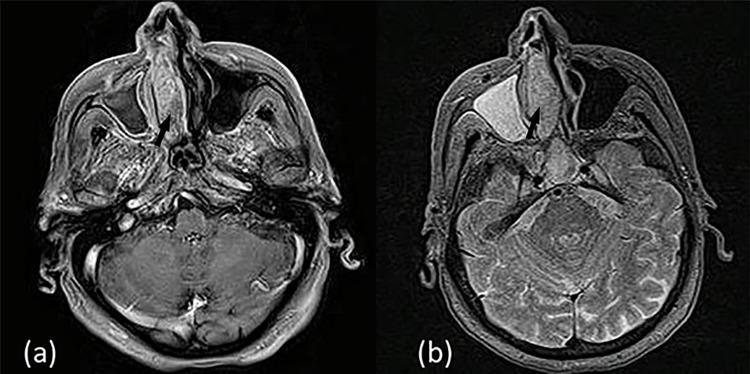

Sinonasal mucosa is an area of high melanocyte density compared to other mucosa-lined sites. Sinonasal mucosal melanomas (SNMM) most commonly arise from the nasal cavity and the paranasal sinuses. Due to their obscure anatomic location and lack of early symptomatology, SNMM are often diagnosed in an advanced stage. The majority of patients who present with symptoms complain of unilateral nasal dysfunction, such as obstruction and epistaxis. We hereby report a case of an 86-year-old female, who presented with a three-year history of progressive right-sided nasal obstruction and recurrent epistaxis. Posterior rhinoscopy and endoscopy revealed a polypoid, fleshy lesion whose coloration varied from mildly pigmented to amelanotic. Inverted sinonasal papilloma was included in the differential diagnosis due to MRI findings. Post-resection histopathology indicated a mucosal melanoma. Typically, amelanotic lesions are rare, more difficult to diagnose and associated with worse prognosis due to both their aggressiveness and delayed diagnosis.

与其他有黏膜衬里的部位相比,鼻窦黏膜是黑素细胞密度较高的区域。鼻窦黏膜黑色素瘤(SNMM)最常起源于鼻腔和鼻窦。由于其解剖位置隐匿且缺乏早期症状,SNMM常被诊断为晚期。出现症状的大多数患者主诉单侧鼻功能障碍,如鼻塞和鼻出血。我们在此报告一例86岁女性患者,她有三年进行性右侧鼻塞和反复鼻出血的病史。后鼻镜检查和内镜检查发现一个息肉样、肉质病变,其颜色从轻度色素沉着到无色素沉着不等。由于MRI检查结果,鉴别诊断中包括了内翻性鼻窦乳头状瘤。切除术后组织病理学显示为黏膜黑色素瘤。通常,无色素沉着的病变很少见,更难诊断,并且由于其侵袭性和诊断延迟,预后较差。